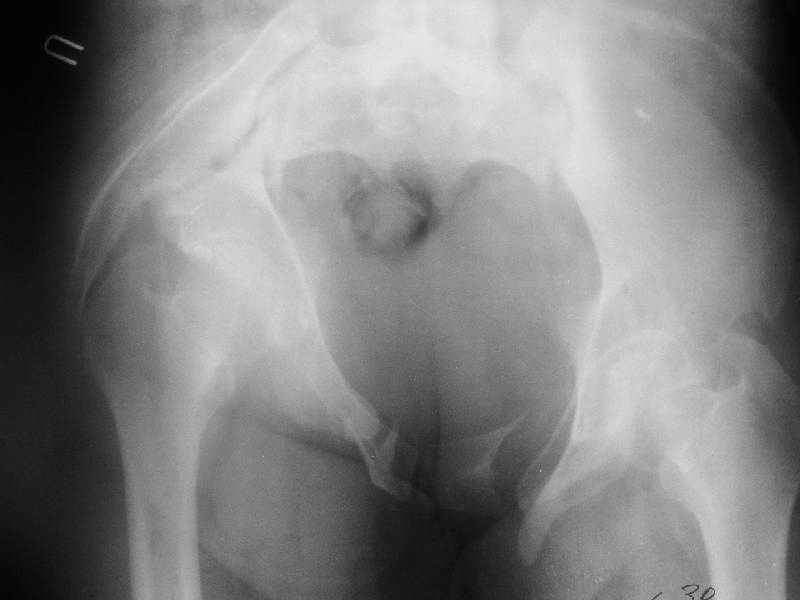

По просьбам коллег отправляем снимки таза: прямая, inlet, outlet, 2 дополнительные компьютерные томограммы.

In other hand, I would like to see the primary X rays, because with 3D-CT alone I cannot classify that fracture into Letournel's classification. Maybe it is a posterior hemitransverse with anterior column fracture.

Госпитализирована больная 27 лет. Травма 1.5 года назад, сбита авто. При поступлении в местной больнице наложен фиксационный аппарат-«передняя рама». Через месяц аппарат снят из-за нагноения, разрешена ходьба с костылями. В послеоперационном периоде отмечалось нагноение забрюшинной гематомы. При обрашении к нам 3 мес назад в области промежности имелся свищ, по месту жительства выполнено иссечение свища, был гнойный затек на бедре, откуда получено до литра гноя, больная ходила с костылями.Свищ зажил 1,5 мес назад При поступлении сейчас укорочение до 5 см, ходит без дополнительной опоры, имеется выраженная хромота.Какой, по вашему, может быть оптимальная тактика оперативного лечения? Ограничиться низведением вертлужной впадины (каким доступом?), выполнить полную реконструкцию передних и задних отделов, одномоментно или поэтапно? Заранее благодарен.